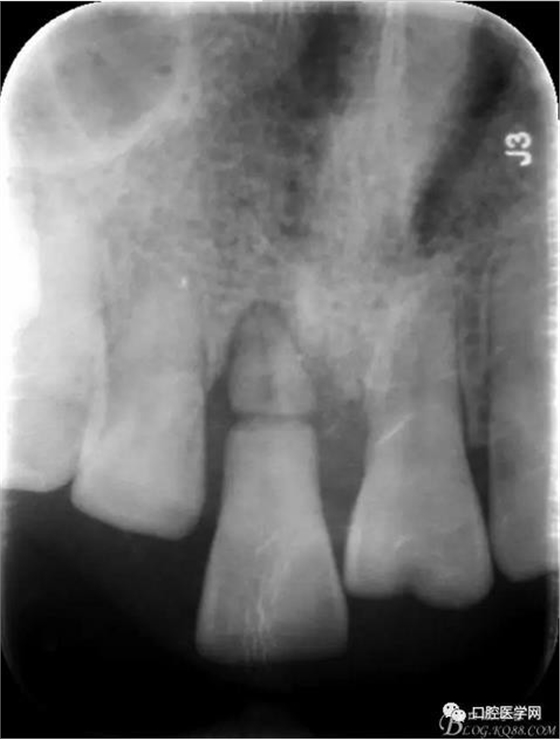

檢 查:11 伸長(zhǎng)約2-3mm,松動(dòng)III°,牙齦退縮3mm

X 光 示:11 根折,根尖無(wú)明顯異常

診 斷:11 根折

圖1 術(shù)前X光片